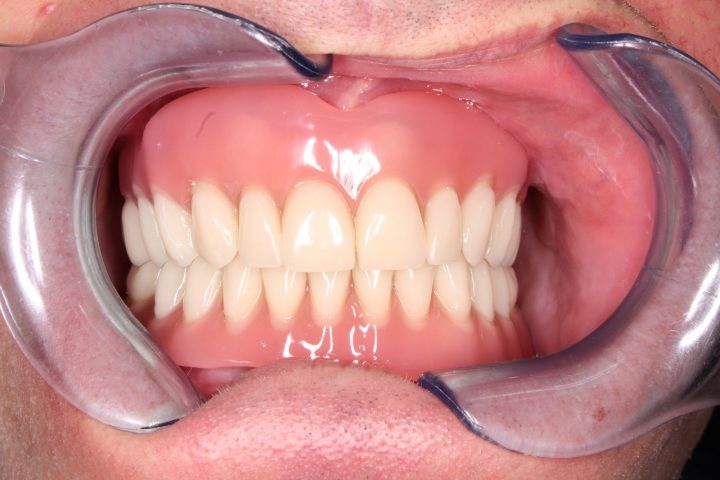

Ibrahim

Ibrahim ist einen von den französischen Patienten, wer früher sowohl oben, als auch unten herausnehmbare Zahnersatz hatte. Die Prothese hatte große Gaumenplatte, und deswegen konnte er die obere nicht tragen.

Er hatte ständig Brechreiz, und hat immer gewürgt, daneben war die Stabilität auch problematisch.

Die Prothesen haben sich ohne Klebstoff bewegt, und er hat sich aufgeregt, wenn er gesprochen hat. Er hatte davon Angst, dass die Prothese einmal ausfällt. Deswegen hat er die Klinik besucht.

Er hat oben und unten festsitzende Prothese auf Implantaten bekommen, womit er restlos zufrieden war. Diese Prothesen bewegen sich nicht weder beim Kauen, noch beim Sprechen.

Dank der Prothese, die keine Gaumenplatte hat, kann er sorglos den Zahnersatz tragen.